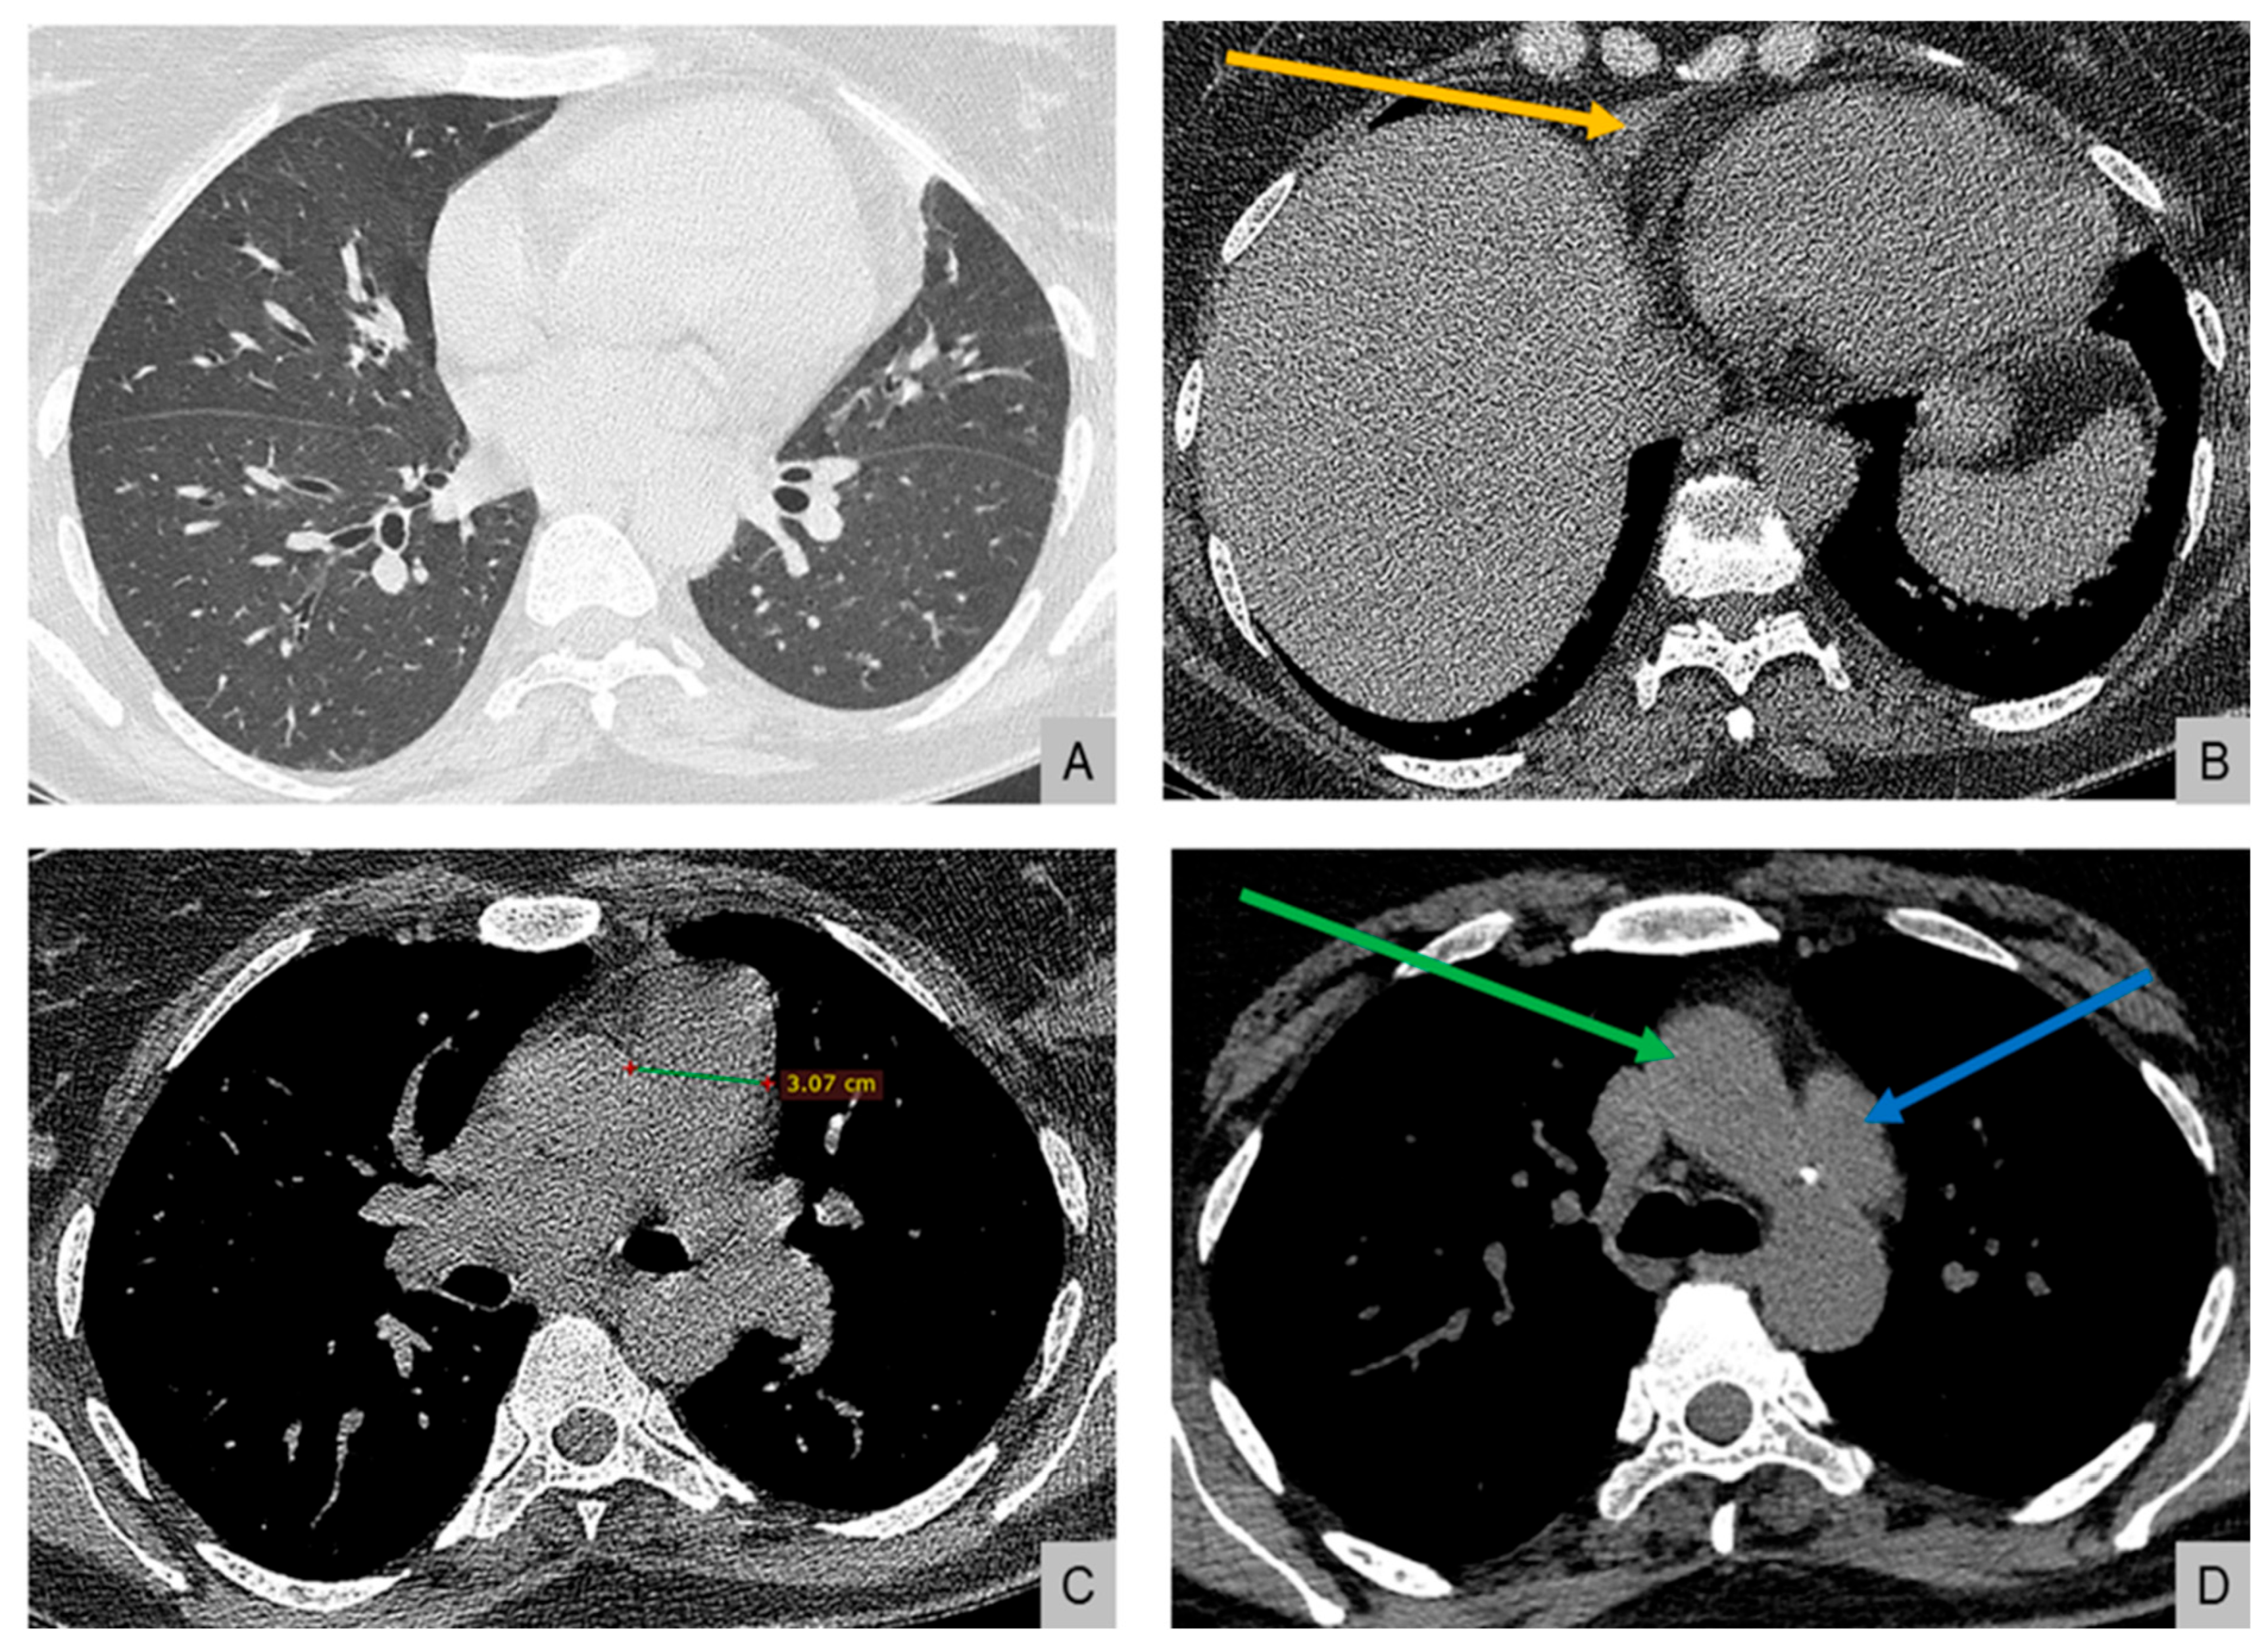

Electrocardiography demonstrated right atrial enlargement and right ventricular strain. Chest radiography (Figure 1) revealed cardiomegaly, pulmonary congestion with enlarged central pulmonary arteries, bilateral pleural effusions, and elevation of both hemidiaphragms.

Figure 1.

Chest radiography on admission demonstrating cardiomegaly with dilation of the central pulmonary arteries, increased interstitial markings with a perihilar “bat-wing” pattern, and bilateral pleural effusions, all indicative of pulmonary congestion. Bilateral elevation of the hemidiaphragms is also noted, possibly related to underlying myopathy.